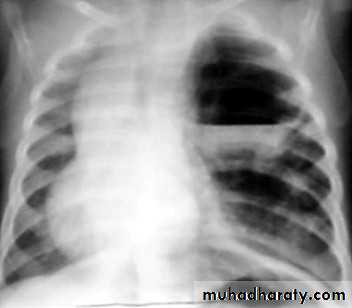

Homogenus opacity of the left hemithorax with shifting of the trachea to the same sidePleural effusion

Homogenus opacity of right lower zone with meniscus signOblitration of right cardiophrenic and costophrenic angles

Homogenus opacity of the right hemithorax

Oblitration of cardiophrenic and costophrenic angles

Shifting of the trachea to the opposite side